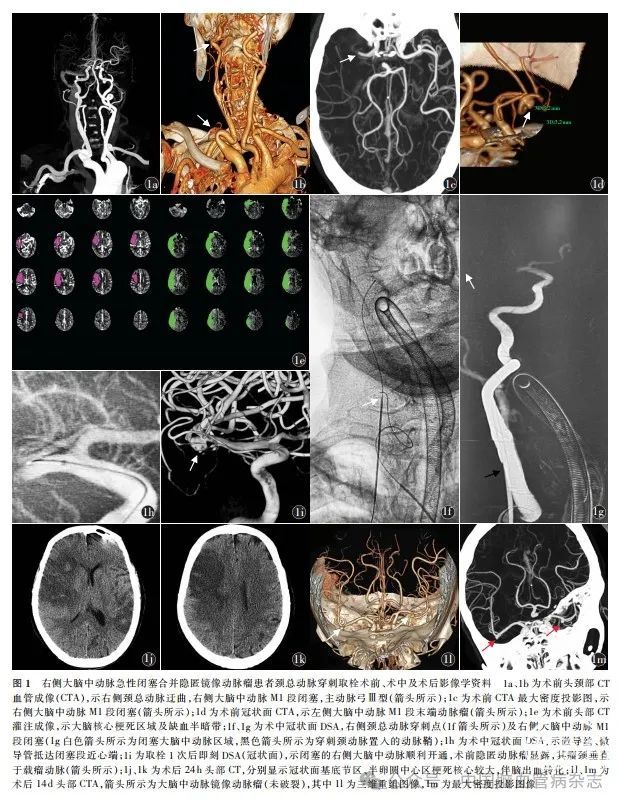

女,77岁,因“突发左侧肢体无力伴言语不能3 h”于2021年8月8日入住西南医科大学附属医院神经内科。入院前3 h,患者因突发左侧肢体无力伴言语不能就诊于赤水市人民医院神经内科,美国国立卫生研究院卒中量表(NIHSS)评分12分,予阿替普酶36 mg静脉溶栓后被送至西南医科大学附属医院神经内科,NIHSS 评分13 分(左上肢4分+左下肢4 分+语言2 分+面瘫2 分+感觉1 分)。既往高血压病史2 年,未规律服用降压药。急查血常规,红细胞计数3. 2 × 1012 / L,血红蛋白98 g / L,血小板计数103 ×109 / L,白细胞计数8. 66 × 109 / L,中性粒细胞计数7. 84 ×109 / L,中性粒细胞白细胞率90. 50%;心电图示心房颤动、快速心室率;Alberta 卒中项目早期CT 评分(Alberta stroke program early CT score,ASPECTS)6分;头颈部CT血管成像(CTA)示主动脉弓Ⅲ型,右侧颈动脉迂曲(图1a,1b),右侧大脑中动脉M1段闭塞(图1a,1c),左侧大脑中动脉M1段末端有1 个3. 2 mm × 3. 2 mm的动脉瘤(图1d);头部CT灌注(computed tomography perfusion,CTP)成像RAPID软件分析显示,核心梗死体积60 ml,缺血半暗带体积178 ml,失匹配比值3. 0(图1e)。患者符合血管内治疗适应证,无绝对禁忌证,获取家属诊疗知情同意书签字后于2021 年8 月8 日行急诊血管内治疗。全身麻醉,穿刺右侧股动脉,DSA显示腹主动脉、颈总动脉、颈内动脉迂曲,主动脉弓Ⅲ型,右侧大脑中动脉M1 段中段闭塞,残端呈“杯口征”。股动脉入路经多次尝试仍无法建立取栓手术的通路,考虑血管解剖路径不佳,遂改为穿刺颈总动脉。置入动脉鞘(6 F,Cordis,美国;图1f),通过动脉鞘送入中间导管(125 cm,5 F,EV3,美国),通过中间导管造影再次确认大脑中动脉闭塞(图1g)。将微导丝(200 cm,Avigo,EV3,美国)及微导管(153 cm,Rebar-18,EV3,美国)送至闭塞段近心端(图1h),并经造影确认在血管真腔。通过微导管送入取栓支架(4 mm × 20 mm,Solitaire FR,EV3,美国),在中间导管辅助下抽拉结合取栓1 次,血管再通,并在原闭塞大脑中动脉末端暴露1个3 mm × 4 mm的隐匿动脉瘤,瘤颈垂直于载瘤动脉,向下方生长(图1i)。颈总动脉穿刺点通过血管封堵器(6 F,Cordis,美国)止血。原闭塞右侧大脑中动脉末端的镜像动脉瘤未进行处理。术后24 h复查头部CT,可见脑梗死合并少量脑出血转化(图1j,1k),继续观察。术后9 d出院,出院时NIHSS评分8分,患者回当地医院进行康复治疗。术后14 d复查头部CTA,提示镜像动脉瘤未破裂(图1l,1m)。术后3个月门诊随访,改良Rankin量表(mRS)评分3 分。术后1、2年进行电话随访,mRS评分分别为2、1分。